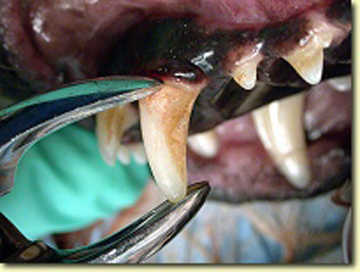

Los problemas que aquejan los tejidos periodontales son varios aunque su etiología primaria siempre es la misma, el alimento y las bacterias que se pegan a los dientes formando la placa dento bacteriana (PDB) y el sarro que destruyen lentamente pero de manera progresiva los tejidos de sostén dental. La enfermedad periodontal es la enfermedad de mayor incidencia y prevalencia en perros y gatos por lo que su diagnóstico, prevención y tratamiento es uno de los retos que el médico veterinario tiene en su trabajo clínico. La enfermedad periodontal es la causa más común de enfermedades como endocarditis bacteriana y artritis infecciosa por lo que el propietario y médico tratante deben de tener especial interés en la prevención y tratamiento de esta patología. La enfermedad periodontal se clasifica dependiendo de los tejidos afectados así como según el grado de destrucción del tejido óseo. Según el tejido afectado como “Gingivitis” cuando afecta la encía libre y papilar, y “Periodontitis” cuando ya afecta el tejido óseo y el ligamento periodontal formando destrucciones del hueso alveolar muy características de la enfermedad denominadas bolsas periodontales las cuales según la forma de destrucción pueden clasificarse como horizontales o verticales. La periodontitis se diagnóstica con una sonda periodontal que es un instrumento que tiene líneas de medición en su punta de trabajo y que se introduce en el surco gingival para medir en milímetros la destrucción ósea alveolar. Otro método de diagnóstico es la radiografía periapical en la cual se puede observar claramente el grado y forma de destrucción ósea alveolar.